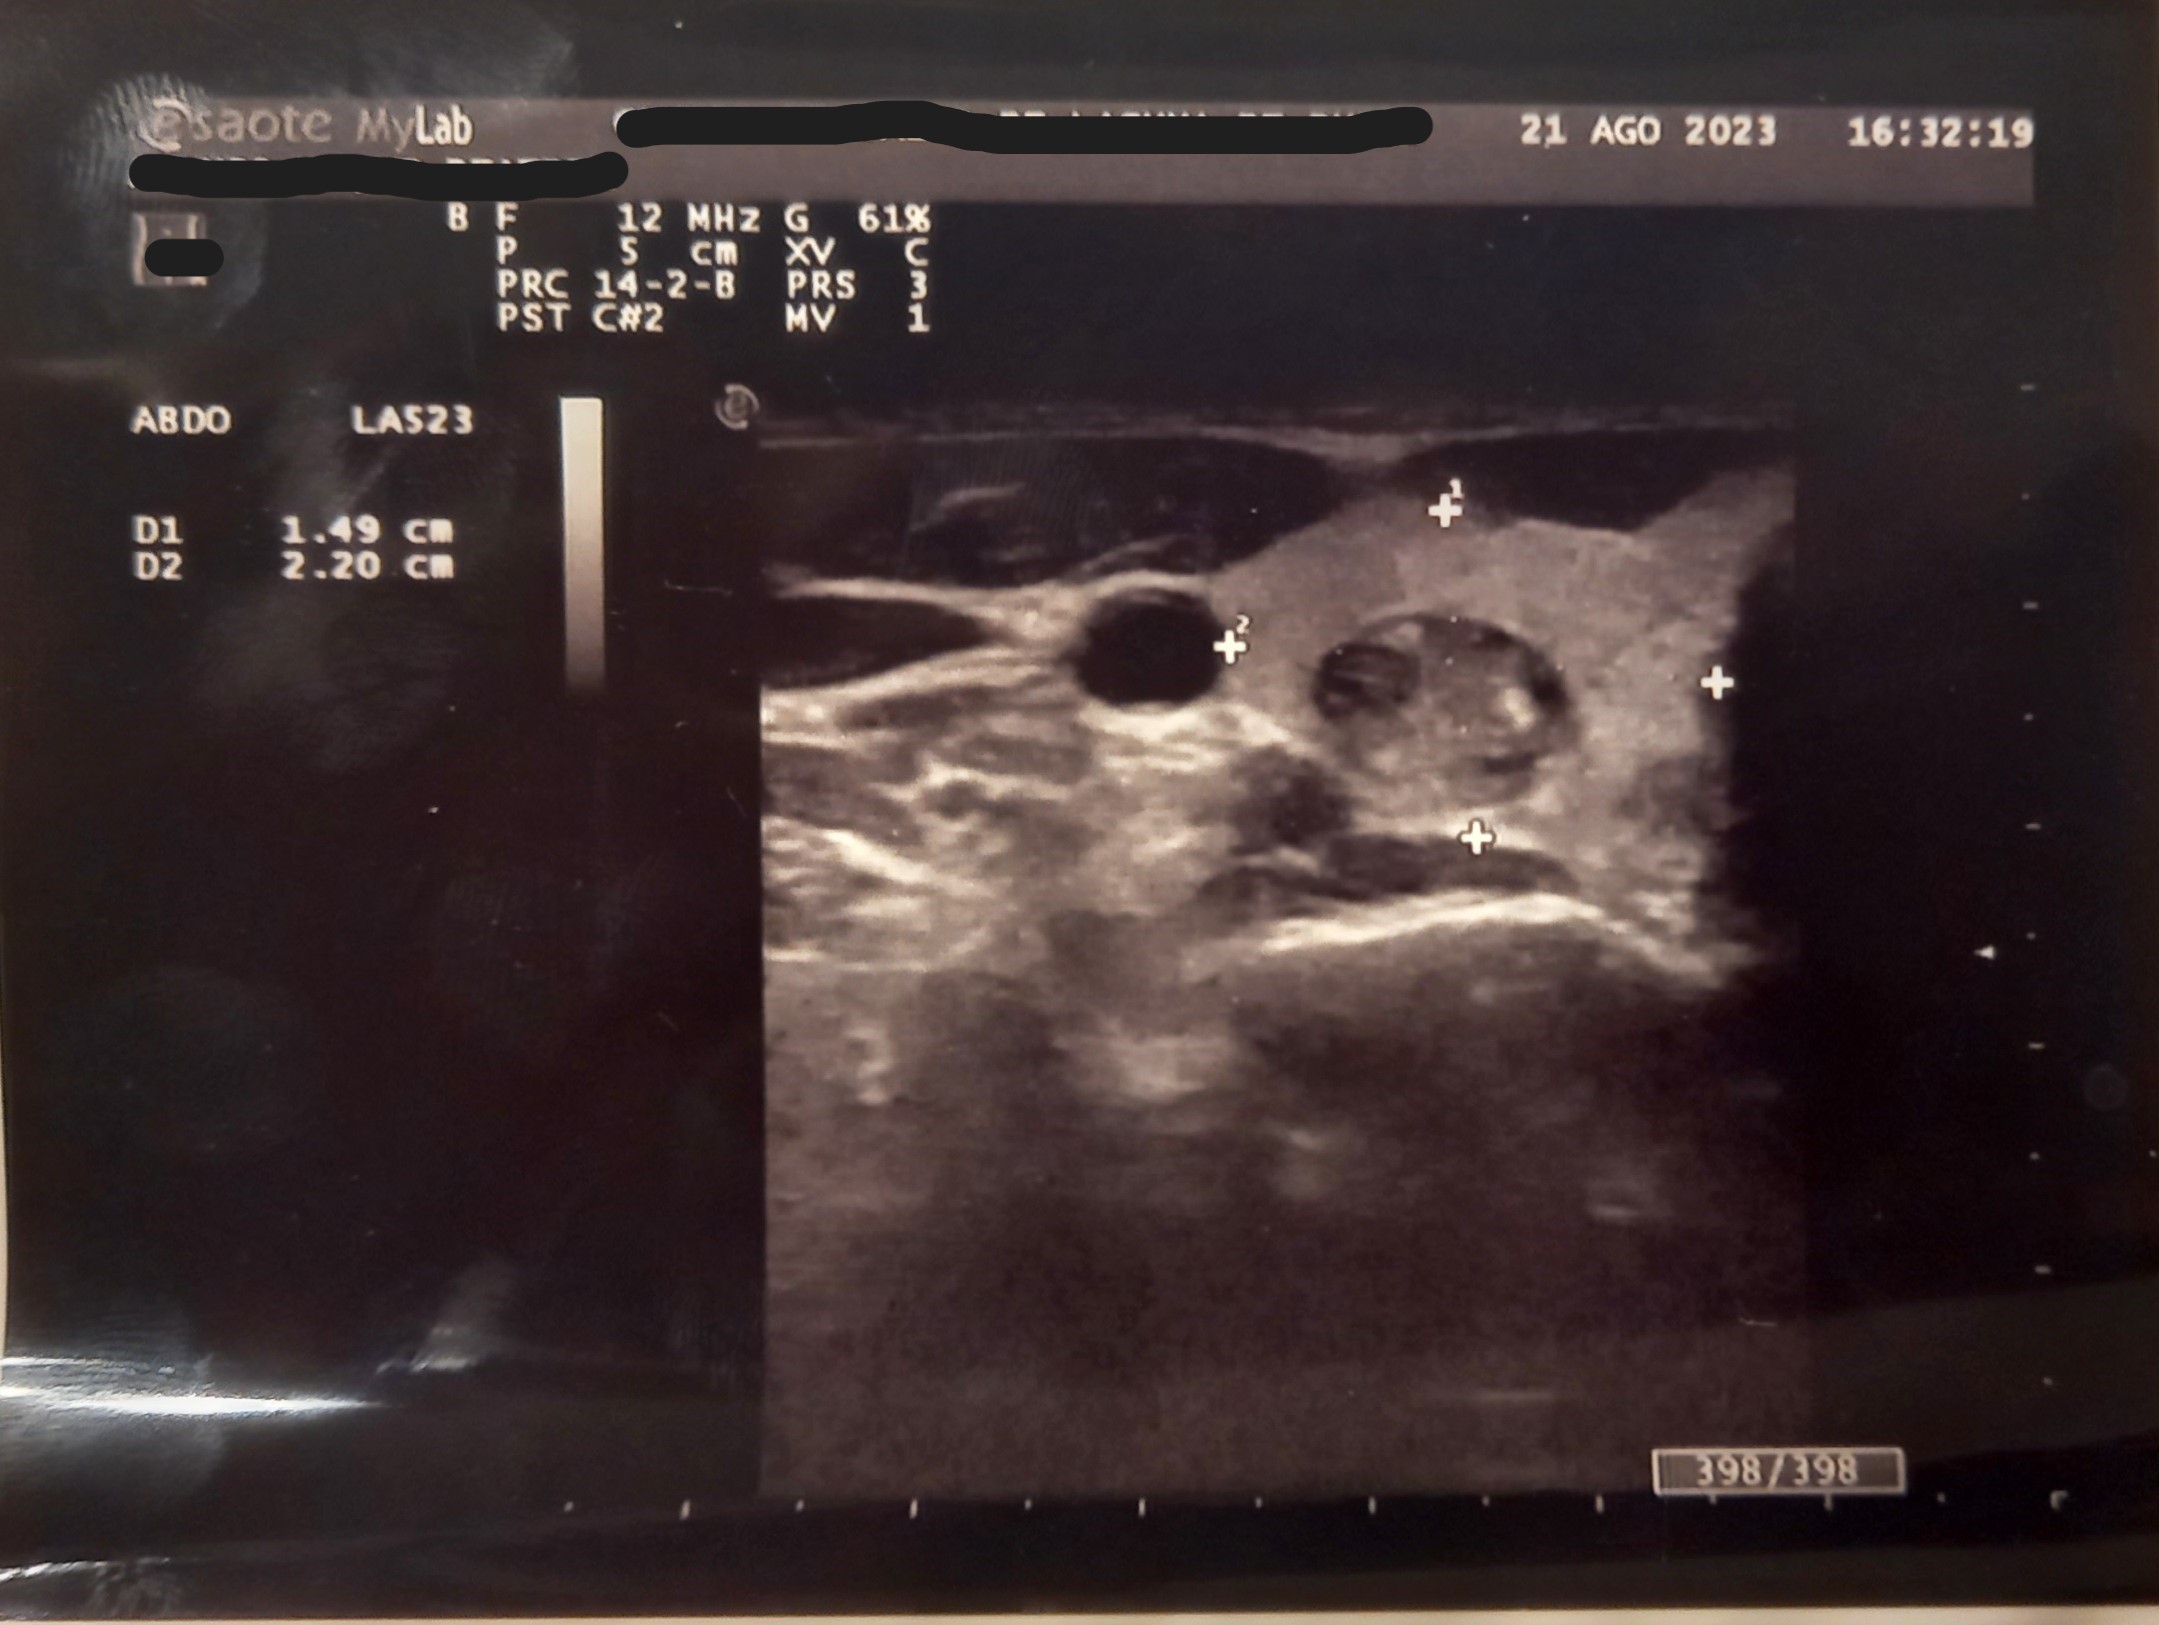

Ecografía en consulta de Atención Primaria. Se observa quiste completo en lóbulo tiroideo derecho, No condiciona aumento importante de tamaño de lóbulo: Dimensiones 14*22*41 mm. Zonas con hiperecogenicidad difusa. Nódulo de características complejas. Ecogenecidad heterogénea zonas anecoicas/hipoecoicas y calcificaciones múltiples. Escala TIRADS: 3.